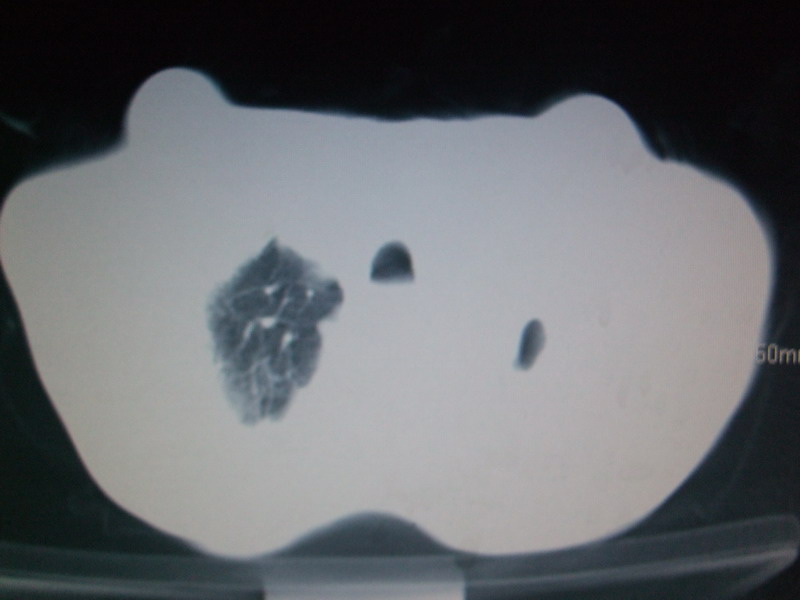

男  70岁,发烧咳嗽4天。盗汗,消瘦。无痰中带血丝,以前有肺tb病史,ct见,双肺tb,左侧胸廓塌陷,左胸膜肥厚粘连。纵隔移位,右侧胸腔积液,大家说说那个心影前左肺舌叶除了肺大炮还有炎症还是干酪性肺炎?有占位吗?我看纵隔淋巴结也大。

1)两肺继发性肺结核并左肺上叶肺不张,支气管扩张。2)双侧胸膜炎(胸膜增厚+少量胸腔积液)。

两肺继发性肺结核并感染,左肺上叶肺不张。建议ct增强。